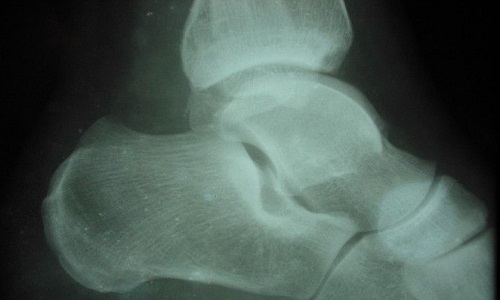

(3)、X线检查:除正、侧位X线摄片外,尚应根据伤情拍摄特殊体位相,如开口位(上颈椎损伤)、动力性侧位(颈椎)、轴位(舟状骨、跟骨等)和切线位(髌骨)等。复杂的骨盆骨折或疑有椎管内骨折者,尚应酌情行体层片或CT检查。

(1)、有外伤史。(2)、上述症状和体征。如肿痛、压痛、畸形等。(3)、X线摄片可见骨折。

由于跟骨及踝部骨折可与距骨骨折同时发生,有时临床鉴别是困难的,多需X线检查确诊。但距骨后突骨折,对经验较少的医生容易与距骨后大小相似的副骨相混淆,后者是一边缘光滑的子骨,同时距骨后缘也无缺损现象,而距骨后突骨折则相反,应注意鉴别。

距骨体骨折多为高处跌下,暴力直接冲击所致。距骨体可在横的平面发生骨折,也可形成纵的劈裂骨折。骨折可呈线状,星状或粉碎性。距骨体骨折往往波及踝关节及距下关节,虽然移位很轻,但可导致上述关节的阶梯状畸形,最终产生创伤性关节炎,因此距骨体骨折预后比距骨颈骨折更差。

(1)距骨颈部及体部骨折:多由高处坠地,足跟着地,暴力沿胫骨向下,反作用力从足跟向上,足前部强力背屈,使胫骨下端前缘插入距骨的颈、体之间,造成距骨体或距骨颈骨折,后者较多。如足强力内翻或外翻,可使距骨发生骨折脱位。距骨颈骨折后,距骨体因循环障碍,可发生缺血性坏死。